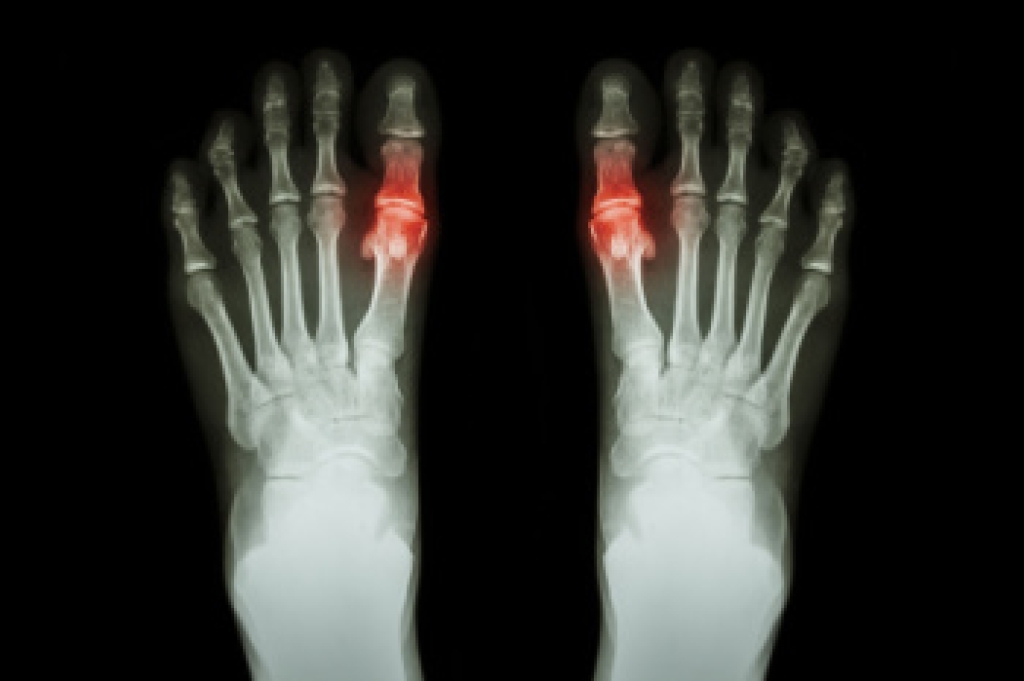

A bunion, also known as hallux valgus, is a deformity of the big toe joint that can cause pain, swelling, and difficulty walking. Surgery is sometimes chosen when conservative treatments no longer provide relief. For middle-aged and older adults, one important consideration is how the procedure may influence balance and gait. Research has shown that correcting the alignment of the big toe can improve stability, reduce pain, and restore more natural walking patterns. However, recovery requires time and rehabilitation, and some individuals may experience temporary weakness or changes in weight distribution. Wearing proper footwear, targeted exercises, and a gradual return to activity are key factors in regaining full function. Each patient’s outcome can vary depending on health, activity level, and severity of the deformity. If you are considering bunion surgery and have concerns about balance or gait, it is suggested that you consult a podiatrist for personalized guidance and appropriate care.

- Removing foot deformities like bunions and bone spurs

- Bunionectomy for painful bunions